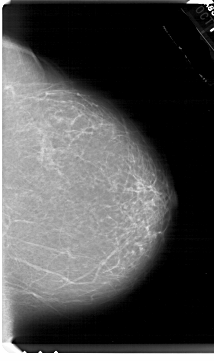

A_1665_1.LEFT_CC

LEFT_CC LINES 6871 PIXELS_PER_LINE 3931 BITS_PER_PIXEL 12 RESOLUTION 43.5 OVERLAY

FILE: A_1665_1.LEFT_CC.OVERLAY

TOTAL_ABNORMALITIES 1

ABNORMALITY 1

LESION_TYPE MASS SHAPE IRREGULAR MARGINS ILL_DEFINED

ASSESSMENT 4

SUBTLETY 4

PATHOLOGY MALIGNANT

TOTAL_OUTLINES 1

BOUNDARY